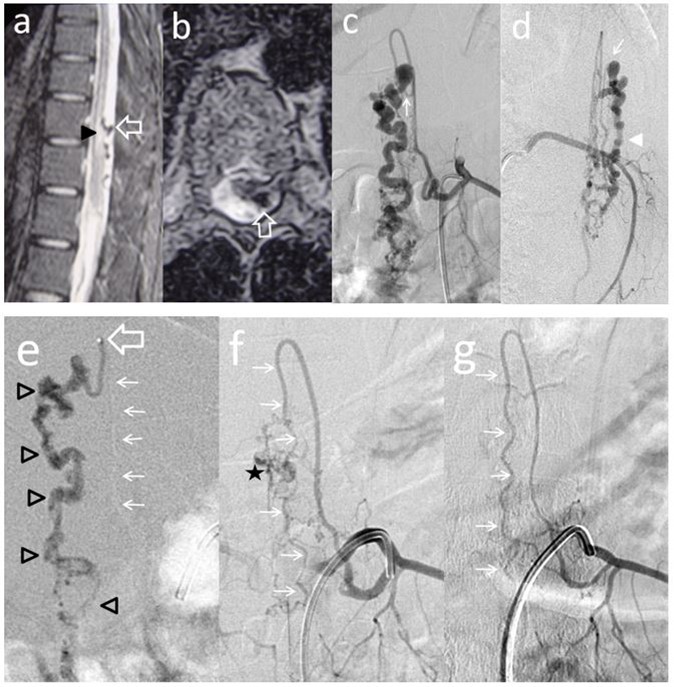

Figure 3.Case # 3: a) T2W MR sagittal and b) axial non contrast spinal MRI, showing flow voids in the dorsal aspect of conus and epiconus (open arrows) with hypersignal extending towards the lower dorsal spinal cord (arrowhead in a). c and d) Segmental left T11 angiogram in AP and lateral projections. The artery branches off to an enlarged ASA (Artery of Adamkiewicz) and also a thinner PSA feeding the PMAVF. The fistula is located posterolaterally (thin arrow in c) and d), draining downwards (arrowhead). e) Injection of 33% n-BCA with rapid microcatheter removal. See the tip of the microcatheter in the curve of the PSA (open arrow). The glue reached the fistulous site and the draining vein (open arrowheads) f) Left T11 angiogram following embolization did not show any shunt and only remnants of the abnormal draining veins were seen (star) with preservation of the ASA axis (thin arrows). g) An angiogram performed 3 months postembolization demonstrated complete eradication of the AVF and preservation of the artery of Adamkiewicz (thin arrows).

Two out of 4 patients were diagnosed and studied preoperatively with both spinal MRI and CT scans, 1 patient with MRI and the other patient with CT/CT Angiography with 3D reconstruction. Large and tortuous flow voids with large to giant venous pouches or pseudoaneurysms (3 of our cases - type c) causing compression of the spinal cord were found lying ventrally and, in another one, posterolaterally to the spinal cord. Hyperintensity in T2W sequences in the spinal cord was noted in all of them. There were no cases where a hemorrhage was exhibited. The angiographic studies confirmed the 4 large or giant pouches at the draining vein fed by ASA and or PSA and ascending (2 cases), descending (1 case) or metameric (1 case) venous drainage. The blood flow was moderate in 1 case and very fast in the other 3 patients (see Table 2 and Figure 1, Figure 2, Figure 3, Figure 4).

We used transarterial approach and a single session achieving complete obliteration of the fistulae while preserving the normal vasculature, mainly the ASA, in all of our 4 cases using either different concentrations of n-bca alone tailored to the blood flow velocity (cases 1,2 and 3), or a combination of coils and onyx 18 (case 4). In this last case, the high flow fistula and the presence of a giant pseudoaneurysm at the venous varix compressing the spinal cord prompted us to deploy coils in the sac and in the draining vein to slow down the blood flow and decrease the chance of distal embolism. To date, we do not have Onyx of higher concentration than Onyx18 available in our country. In high flow macrofistulae, our strategy to slow down the flow to allow casting of the polymerizing embolic mixture in the fistulous site avoiding distal embolism includes lowering mean arterial pressure down to 60-70 mm Hg pharmacologically, by embolizing with concentrations of 66% of n-bca in lipiodol, as well as the placement of detachable coils in the event of very high flow with pseudoaneurysms at or very close to the fistulous site as a first step, to trap the liquid embolic material injected as second step (see Figure 1, Figure 2, Figure 3, Figure 4).